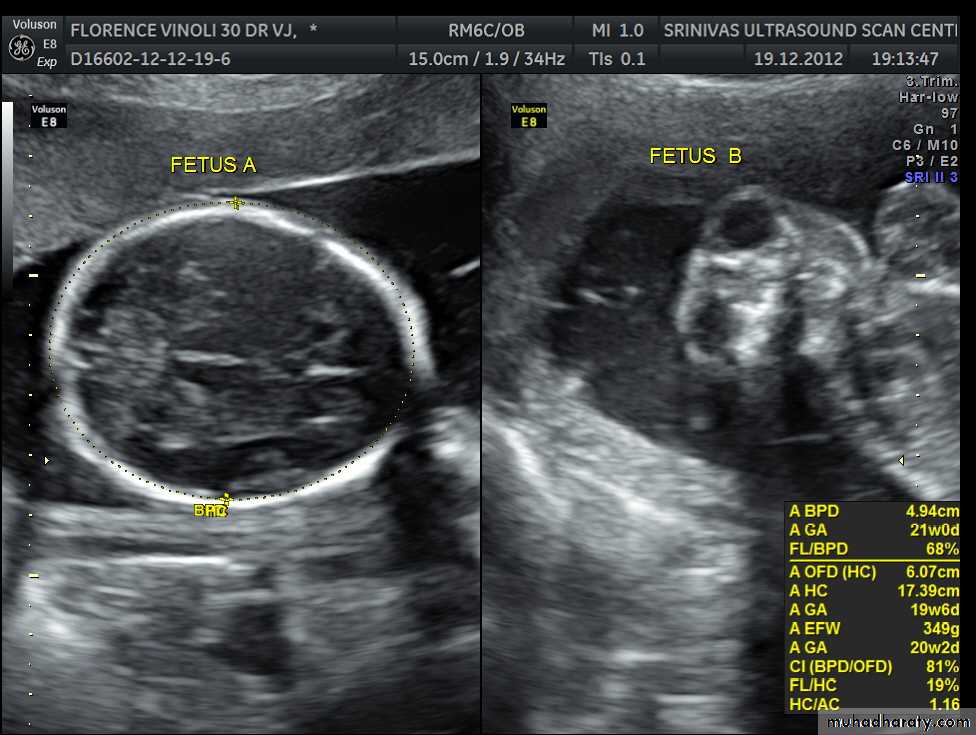

Mosul Medical College /radiology department2016BPD together with head circumference (HC), abdominal circumference (AC), and femur length (FL) are computed to produce an estimate of fetal weight. In the second trimester this may be extrapolated to an estimate of gestational age and an estimated due date (EDD) .

The BPD should be measured on an axial plane that traverses the thalami, and cavum septum pellucidum. The transducer must be perpendicular to the central axis of the head, and thus the hemispheres and calvaria should appear symmetric.